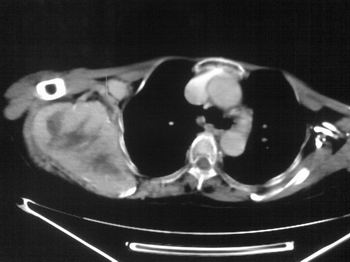

以下是引用zhangxu5888在2007-9-11 16:25:00的发言:[br]有侧肩胛骨溶骨性破坏且见软组织成分,增强软组织强化明显,中央见低密度坏死区!根据病史10年,考虑良性肿瘤恶性变!性质待定!

以下是引用老爱克斯新网客在2007-9-11 18:22:00的发言:[br]应该是良性肿瘤恶变,但因晚期破坏严重不能见到原来肿瘤征象无法判断,